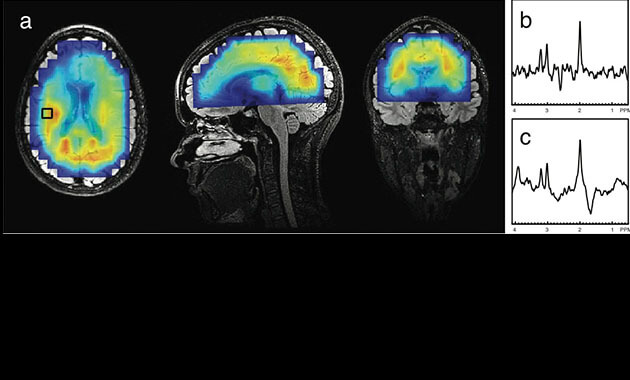

A metabolite map and sample spectra (long-echo and short-echo) from a healthy volunteer, acquired using automatically-prescribed slice-selected 3D MRSI. The acquisition covered most of the brain volume, while maintaining the high quality of spectral data.